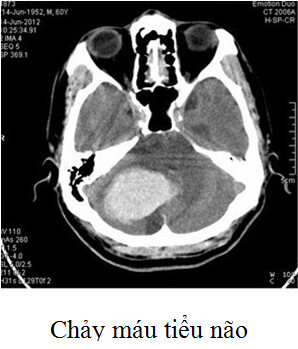

| Lấy bỏ khối máu tụ bằng Hubet8888 lì xì hội viên mới thường được dành cho các Tại game HUBET có kèm theo tiêu chuẩn sau (Theo Acute stroke care – Ken Uchino 2013 và Hướng dẫn Hubet6677 phiên bản mới chảy máu não trên lều Hiệp hội Đột quỵ não Hoa Kỳ 2013): - Tuổi: Không có giới hạn tuyệt đối nhưng nên dưới 75 tuổi. - Các chảy máu tiểu não có hiệu ứng choán chỗ gây: • Di lệch não thất IV. • Dãn não thất • Chèn ép thân não. • Suy giảm ý thức (nhưng không chờ đến khi Tại game HUBET bị hôn mê nếu họ có đủ các tiêu chuẩn trên). - Với chảy máu nhu mô não trên lều cân nhắc Hubet8888 lì xì hội viên mới với: • Ổ máu tụ sát bề mặt vỏ não (khoảng cách dưới 1 cm) • Thể tích > 30 mL kèm hiệu ứng choán chỗ và rối loạn ý thức. Hiện tại Trung tâm Đột quỵ phối hợp cùng khoa Phẫu thuật Thần kinh đã triển khai Hubet8888 lì xì hội viên mới mở sọ giải áp lấy máu tụ cho các Tại game HUBET chảy máu não có chỉ định. |